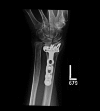

Background: A single volar locking plate (VLP) is now frequently used for open reduction and internal fixation (ORIF) of many types of distal radius fractures. Comminuted intra-articular distal radius fractures (AO C3-type) are typically the most challenging to surgically treat. No studies directly address the adequacy of a VLP alone for maintaining reduction of AO C-type fractures. We hypothesized that a single VLP provides an effective method for maintaining reduction for these fractures.

Methods: We retrospectively evaluated radiographs of a series of AO C-type fractures. Seventy-seven patients with 77 AO C3-type fractures were identified from billing records and were eligible for the study. All patients were treated by fellowship-trained hand surgeons. Radiographs at the time of union were compared to those from immediately postoperatively.

Results: Sixty-nine of 77 (89.6 %) fractures treated with VLP fixation alone for AO C3-type distal radius fractures united without loss of reduction. Eight of 77 (10.4 %) patients treated with VLP for AO C3 fractures lost reduction. The most common fracture fragment to lose reduction was the lunate fossa (5 of 8); loss of reduction of the scaphoid fossa die-punch fragment (2 of 8) and the radial styloid (1 of 8) were also seen.

Conclusions: The majority (89.6 %) of AO C3-type fractures treated with a single volar locking plate come to union without loss of reduction.